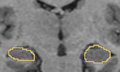

• Segmentation of the hippocampus using a multi-scale shape based method.

We represent and learn the shape in a multi-scale method and then perform the segmentation of the hippocampus.

The code has been written and the method is being tested on multiple data sets.